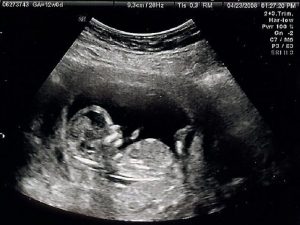

1. 超聲檢查

超聲心動圖是在超聲或超聲波的幫助下獲得心臟醫(yī)學(xué)圖像的過程。它允許醫(yī)生通過將心臟暴露于超聲波并檢測在撞擊心臟壁或心室后反射回來的波來獲得心臟的移動或?qū)崟r圖像。超聲心動圖的過程是無痛和安全的。